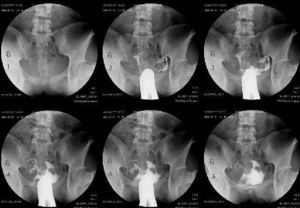

6、都卜勒超聲、CT掃描、MIR可顯示轉移程度。

放療機(1)放射治療的適應證

1)原發腫瘤巨大,浸潤較深,接近或累及尿道、陰道及肛門,手術切除困難之鱗癌患者,術前放療可使腫瘤縮小,以提高切除率,並保留鄰近器官功能。

2)手術切緣距腫瘤太近,切除較姑息者。

3)老年患者或其他原因不宜手術者。

4)年輕患者陰蒂附近小的原發癌,要求保留陰蒂者。

5)晚期外陰癌採用放療和手術綜合治療以代替創傷大,病人不願接受的盆腔臟器切除術。

6)術後復發而難以再切除的外陰癌。